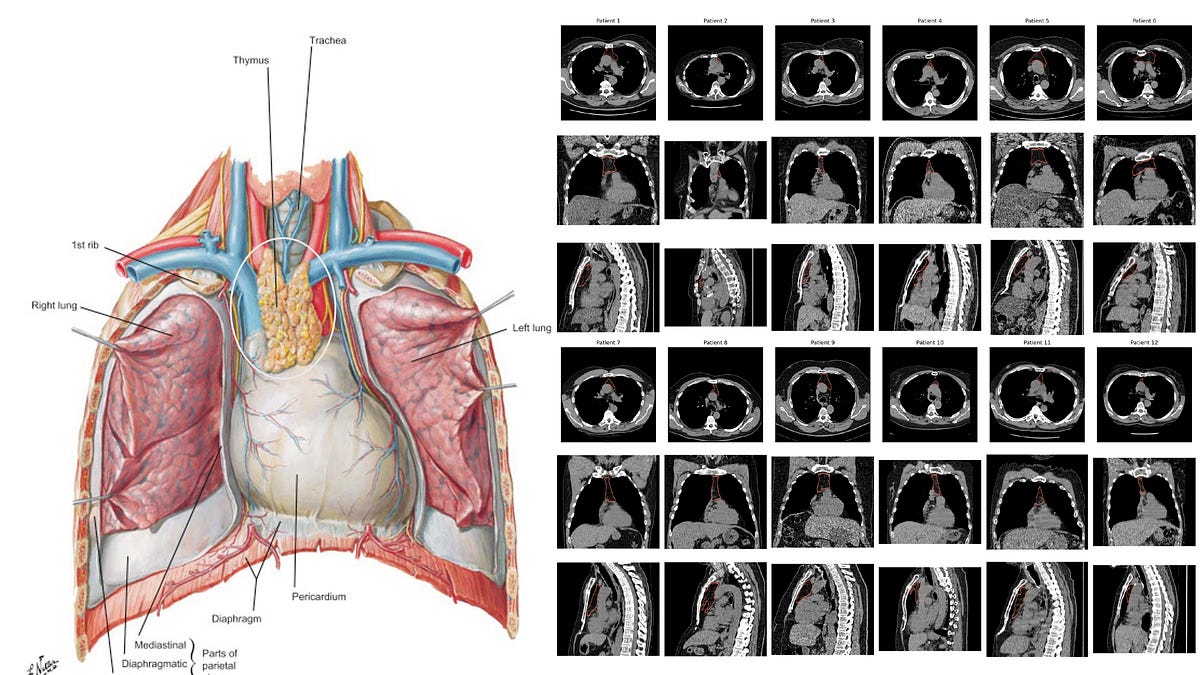

Your Thymus and Your Healthspan - Ground Truths | Eric Topol

Our thymus gland plays a central role in the development of our immune system, specifically for s...